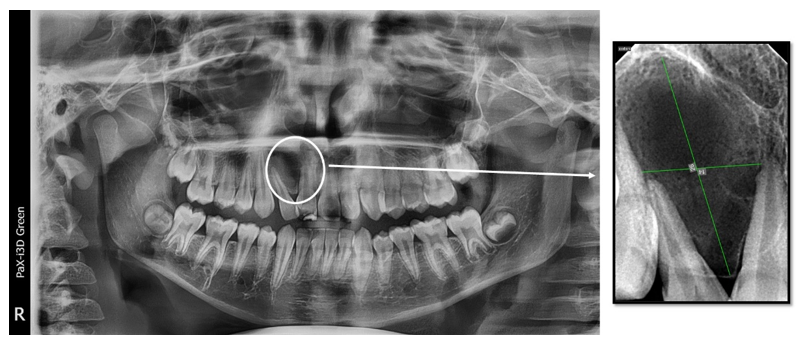

The panoramic radiograph showed a periapical radiolucency between the central and lateral upper right incisors (Teeth # 12 and 11), and a confirmatory periapical radiograph revealed a large, well-defined radiolucency in the periapical region between the two teeth with severely diverged roots (Figure 2).

Figure 2 A panoramic radiograph shows tilted roots of the right lateral incisor due to pressure of the periapical lesion (circle). A preapical radiograph shows a large periapical lesion (14x26mm) with diverged roots of related teeth(# 12 and 11).

After 24 months, follow-up radiographs showed up-righting of tilted roots and a decrease in radiolucency of the lesion, reflecting healing with new bone formation. The severe displacement was corrected, and the patient no longer required orthodontic treatment (Figure 5).

Figure 5 The post-operative radiograph (A) shows the extension of the periapical lesion and tilted roots, and the radiograph after 24 months (B) shows the healing of the periapical lesion and straightening of the tilted roots.